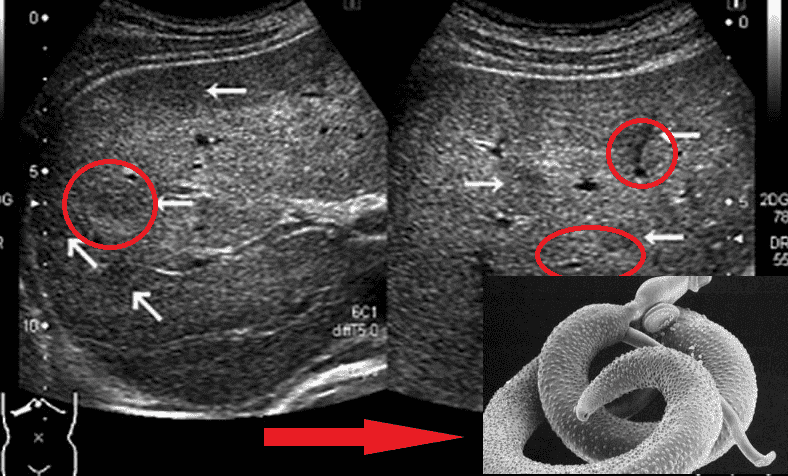

Εκπρόσωποι των ελμινθίων που προσβάλλουν ζωτικά όργανα είναι οι Taenia solium, Echinococcus (Echinococcus granulosus), Trichinella (Trichinella spiralis). Ο Echinococcus είναι το προνυμφικό στάδιο του ελμινθίου του γένους Echinococcus. Υπάρχουν πολλά είδη παρασίτων.

Είμαι ιατροδικαστής εδώ και πολλά χρόνια. Έχω δει τα πράγματα που με ανατριχιάζουν μόνο που το σκέφτομαι. Οι άνθρωποι υποτιμούν τους κινδύνους, νομίζουν ότι τα παράσιτα είναι σκουλήκια που ζουν στο έντερο. Αλλά αυτό δεν είναι έτσι. Υπάρχει ένας τεράστιος αριθμός διαφορετικών τύπων παρασίτων. Για παράδειγμα, υπάρχουν μικροσκοπικά αλλά εξαιρετικά τοξικά παράσιτα. Δηλητηριάζουν τον οργανισμό, εισέρχονται στην κυκλοφορία του αίματος, στην καρδιά, την δηλητηριάζουν με τις τοξίνες, προκαλούν ισχαιμία, καρδιακή ανεπάρκεια, υπέρταση και, ως αποτέλεσμα, έμφραγμα του μυοκαρδίου και εγκεφαλικό επεισόδιο. Μένουν στους πνεύμονες και στο ήπαρ, διεισδύουν στον εγκέφαλο και ζουν ακόμη και στα μάτια!